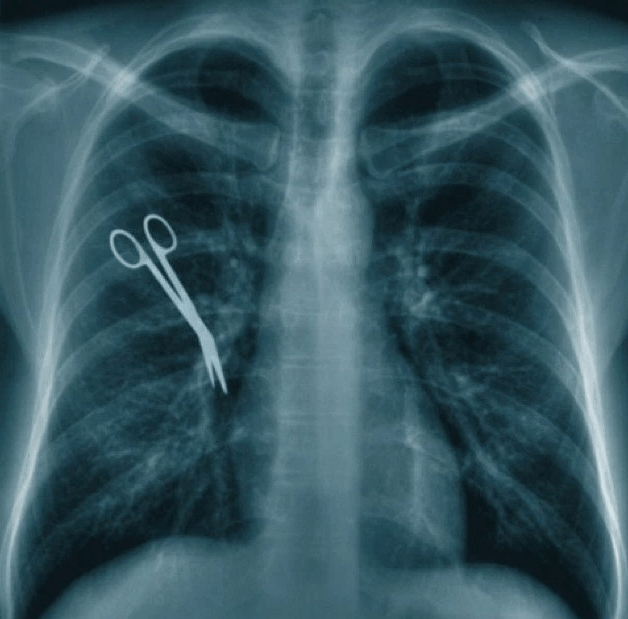

Retractors are like scissors (as you can see in the picture above), except instead of sharp ends they have dulled, wide edges. They’re used in surgery to carefully pull objects out of your organs without causing any damage. It’s also worth noting that they definitely don’t belong inside a human body. Daryoush Mazarei found out the hard way just how long a person can endure with a pair of those stuck inside his body.

After a routine surgery where fluid was being drained from a problematic area of his chest, Mazarei felt that his recovery wasn’t going the way it should be. He was in much more pain than the doctors had expected, and he wasn’t appearing to be getting better. Frustrated physicians and physical therapists eventually concluded that Mazarei was crazy, and was experiencing phantom pain because he was frail. It was only when they ran a CT scan on his body that they realized the horrible mistake that had been made.

The same doctors that took their time realizing something was wrong made haste to take those retractors out. While they did get them out clean and Mazarei’s now on the road to recovery, he suffered needlessly for an entire month and almost died because of their careless mistake and dismissive attitude when he told them something was still wrong. Because of this, he’s begun filing against the hospital that botched his surgery so badly.